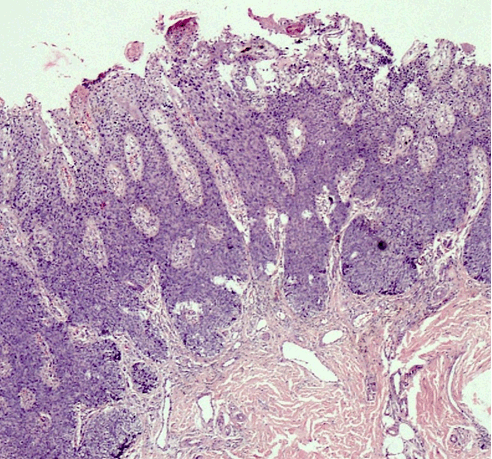

Herein, we report a case of a 40-year-old normotensive, non-diabetic, euthyroid male patient who presented with a non-healing erythematous slightly scaly plaque involving the volar and dorsal aspects of left thumb from last eight months (Figure 1) and (Figure 2). There was history of pruritus and slight burning sensation. There was a history of application of potent topical steroids for few months with no response. A punch biopsy was done which confirmed the diagnosis of eczema psoriasis and Bowen's disease. On histopathology, the patient showed thickened epidermis with full thickness dysplasia of squamous epithelium and atypical keratinocytes with numerous mitotic figures. The basement membrane was intact with no focus of invasion or solar elastosis (Figure 3) and (Figure 4). Thus a diagnosis of Bowen's disease was made. The patient was put on topical 5-fluorouracil and is doing well. | ||||||

Bowen's disease (BD) is a form of intra-epidermal or in-situ squamous cell carcinoma with a small potential for invasive malignancy, and commonly involves chronically photo-exposed areas, especially head and neck region. Commonly a persistent, non-elevated erythematous scaly and crusted plaque is seen. Bowen's disease may occur at any age in adults, but is rare before the age of 30 years; most patients are aged over 60. Any site may be affected, although involvement of palms or soles is uncommon. Bowen's disease occurs predominantly in women in whom about 60-85% of patients have lesions on the lower leg, usually in previously or presently sun-exposed areas of skin. Chronic ultraviolet radiation exposure, arsenic exposure, human papillomavirus and immunosuppression are the various aetiological factors [1] [2] [3]. Histopathology is characterized by full-thickness dysplasia of the epidermis, with loss of the normal maturation of its components. Keratinocytes are atypical and disorderly, often described as having a windblown appearance. Basement membrane is intact. Topical 5-fluorouracil, imiquimod, photodynamic therapy, cryotherapy and excision are the various treatment modalities [4]. | ||||||